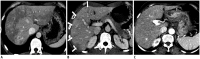

During chemotherapy in patients with gastrointestinal malignancy, the hepatic lesions may occur as chemotherapy-induced lesions or tumor-associated lesions, with exceptions for infectious conditions and other incidentalomas. Focal hepatic lesions arising from chemotherapy-induced hepatopathies (such as chemotherapy-induced sinusoidal injury and steatosis) and tumor-associated eosinophilic abscess should be considered a mimicker of metastasis in patients with gastrointestinal malignancy. Accumulating evidence suggests that chemotherapy for gastrointestinal malignancy in the liver has roles in both the therapeutic effects for hepatic metastasis and injury to the non-tumor bearing hepatic parenchyma. In this article, we reviewed the updated concept of chemotherapy-induced hepatopathies and tumor-associated eosinophilic abscess in the liver, focusing on the pathological and radiological findings. Awareness of the causative chemo-agent, pathophysiology, and characteristic imaging findings of these mimickers is critical for accurate diagnosis and avoidance of unnecessary exposure of the patient to invasive tissue-based diagnosis and operations.